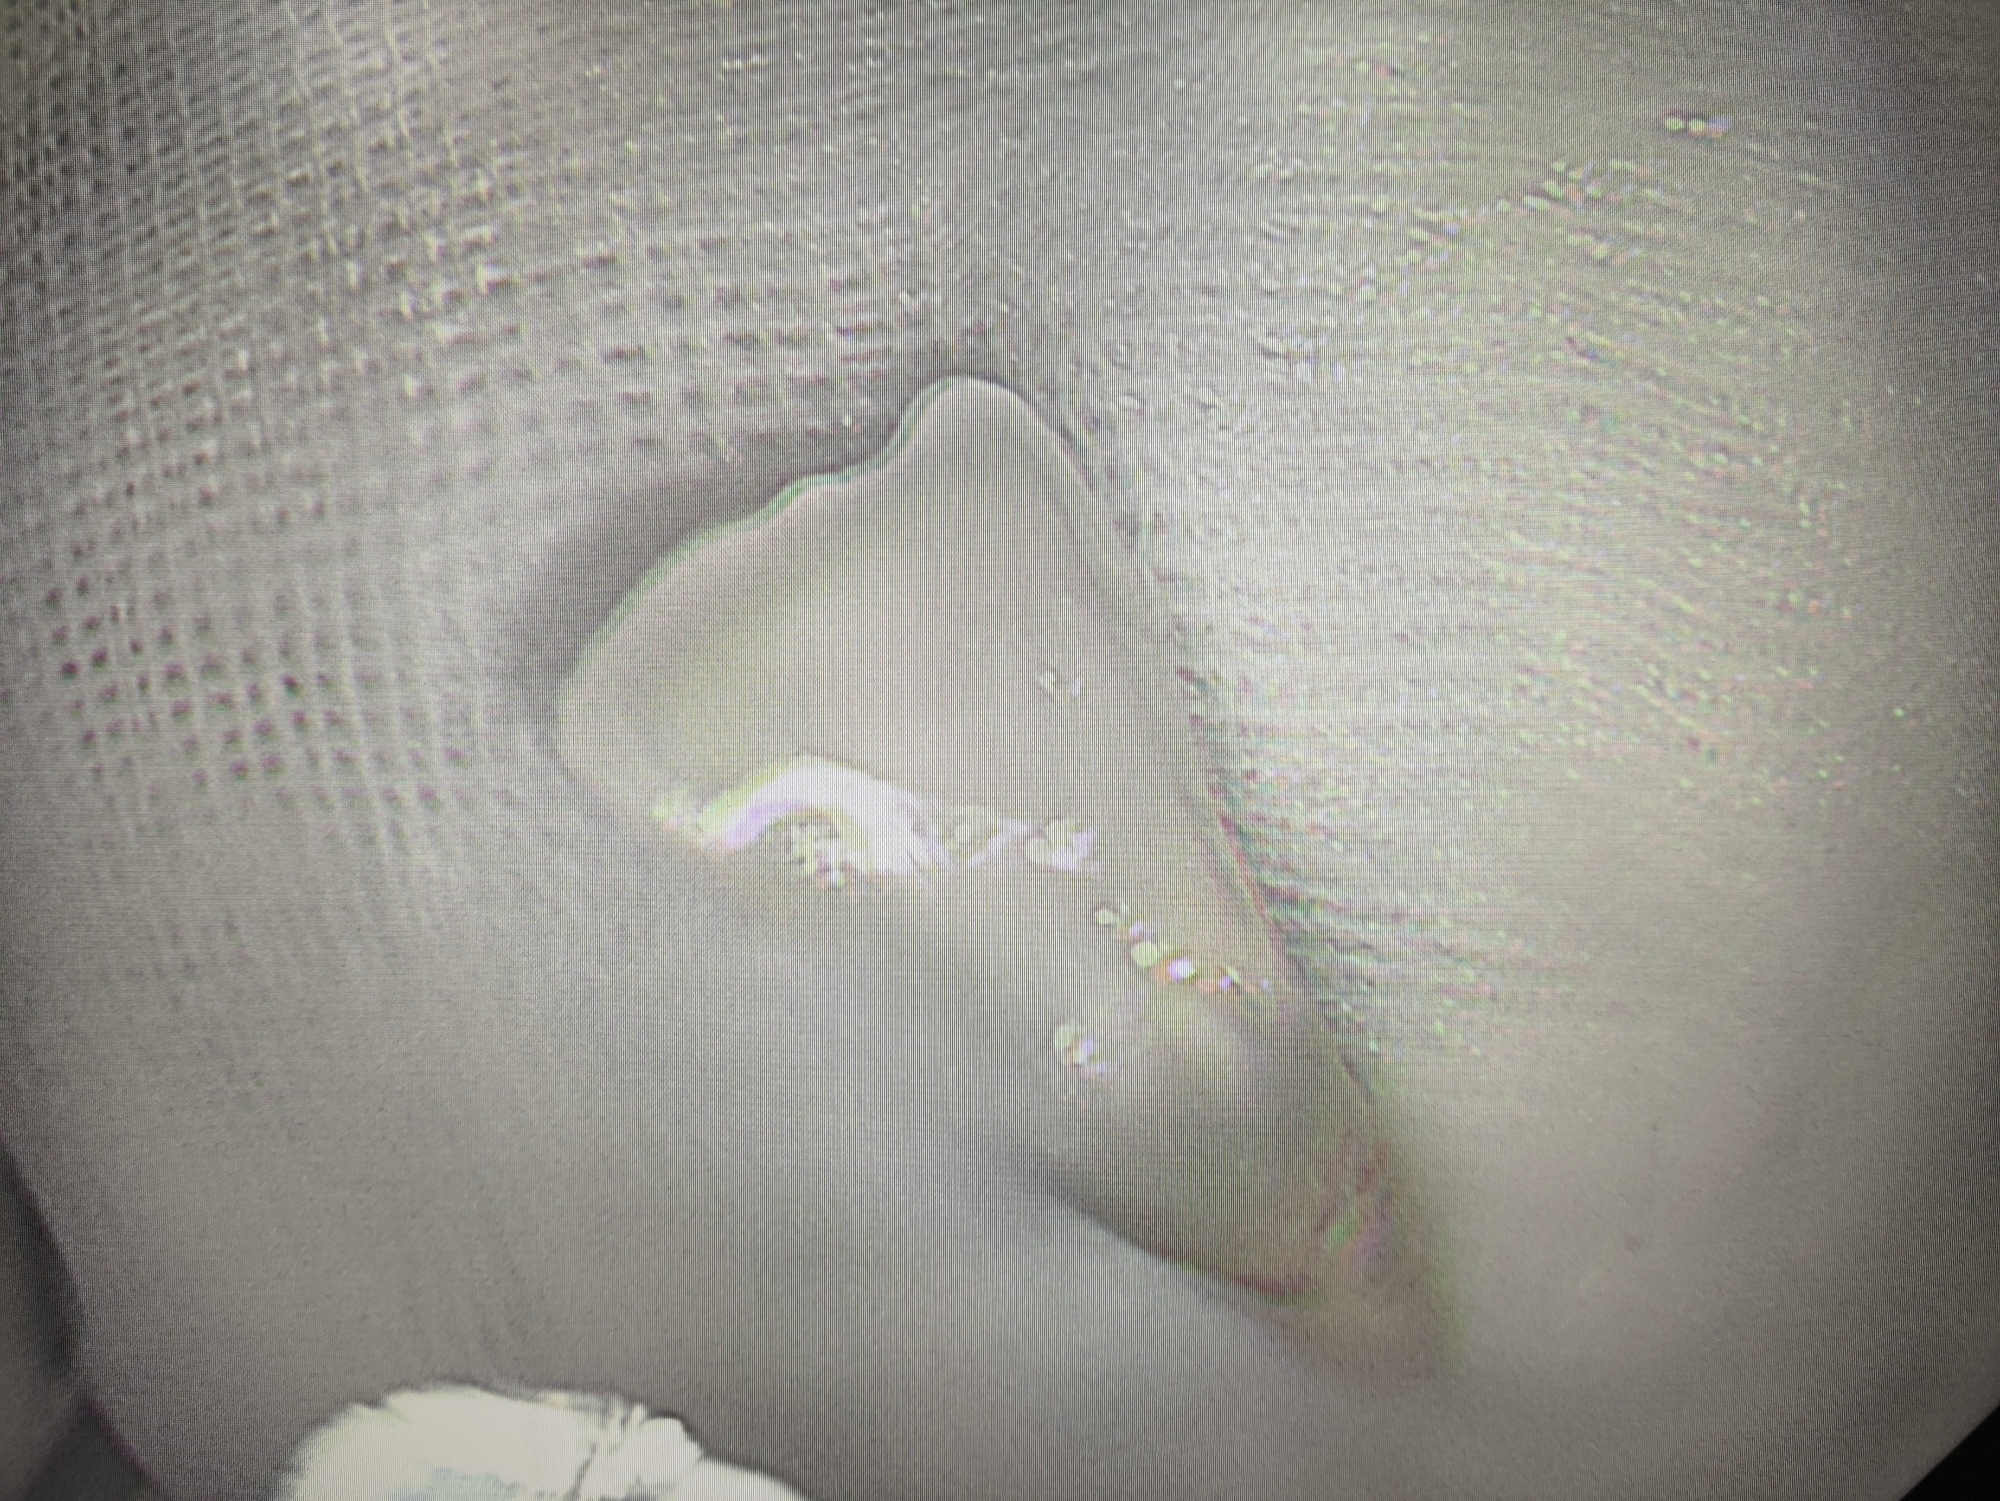

图为从患者咽部取出的牙齿

经过耐心探查,终于在气道入口处发现了那枚脱落的牙齿——它正随着老人的呼吸上下滑动,稍有不慎就可能坠入气道,后果不堪设想。考虑到牙齿位置特殊,若用异物钳直接夹取,极易因滑脱引发窒息,医护团队果断更换网篮器械,调整角度、精准瞄准,在反复尝试后,终于稳稳将牙齿套住并取出。